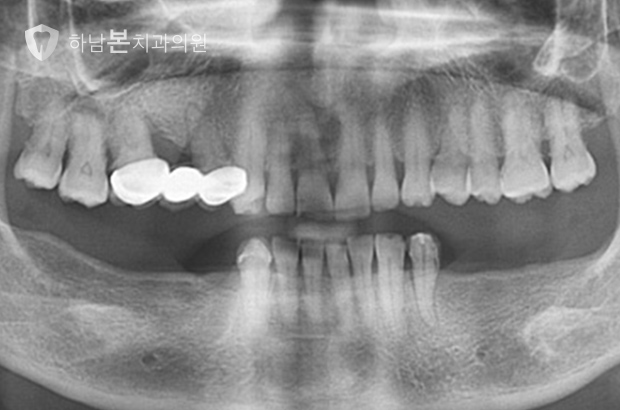

멀티 임플란트 케이스

CASE 1 / 상하악 양쪽 대구치 8개 / 멀티 임플란트

CASE 2 / 상하악 양쪽 전치, 소구치, 대구치 13개 / 무치악 임플란트

CASE 3 / 하악 양쪽 전치, 소구치, 대구치 7개 / 무치악 임플란트